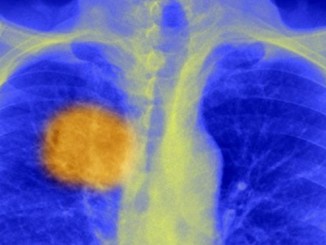

Kanserin ‘zayıf noktası bulundu’